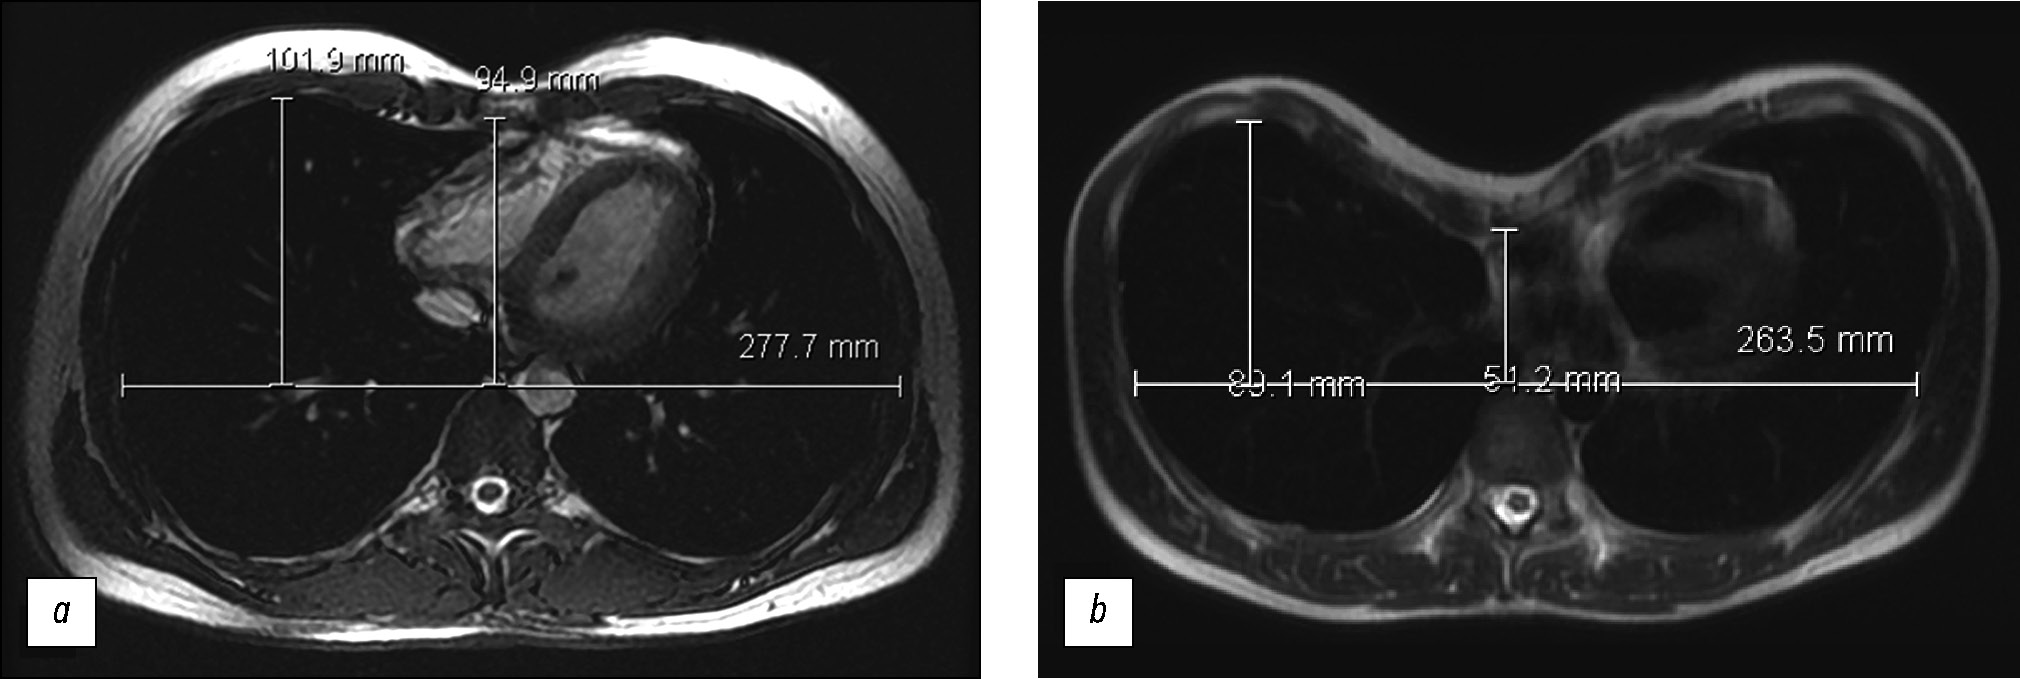

Correction Index

The mean correction index in this study was 31.5 (±11) (Fig. 3). The correction index increased in tandem with the Haller index (the degree of chest wall deformity), as indicated by the statistical analysis P < 0.05 (Fig. 4). For instance, the mean correction index was 13, 24, and 35 in patients with mild, moderate, and severe PE, respectively.

Fig. 3. Chest magnetic resonance imaging at the level of maximum deformity; (a) the correction index of 7%; (b) the correction index of 32%.